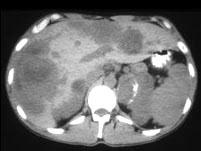

问题 男,37岁,阵发性高血压1个月余,请结合所提供图像,选择最佳答案 ( )

选项 A、肝转移瘤 B、原发性肝癌 C、左侧恶性嗜铬细胞瘤 D、左侧肾上腺转移瘤 E、左侧肾上腺癌

答案 AC